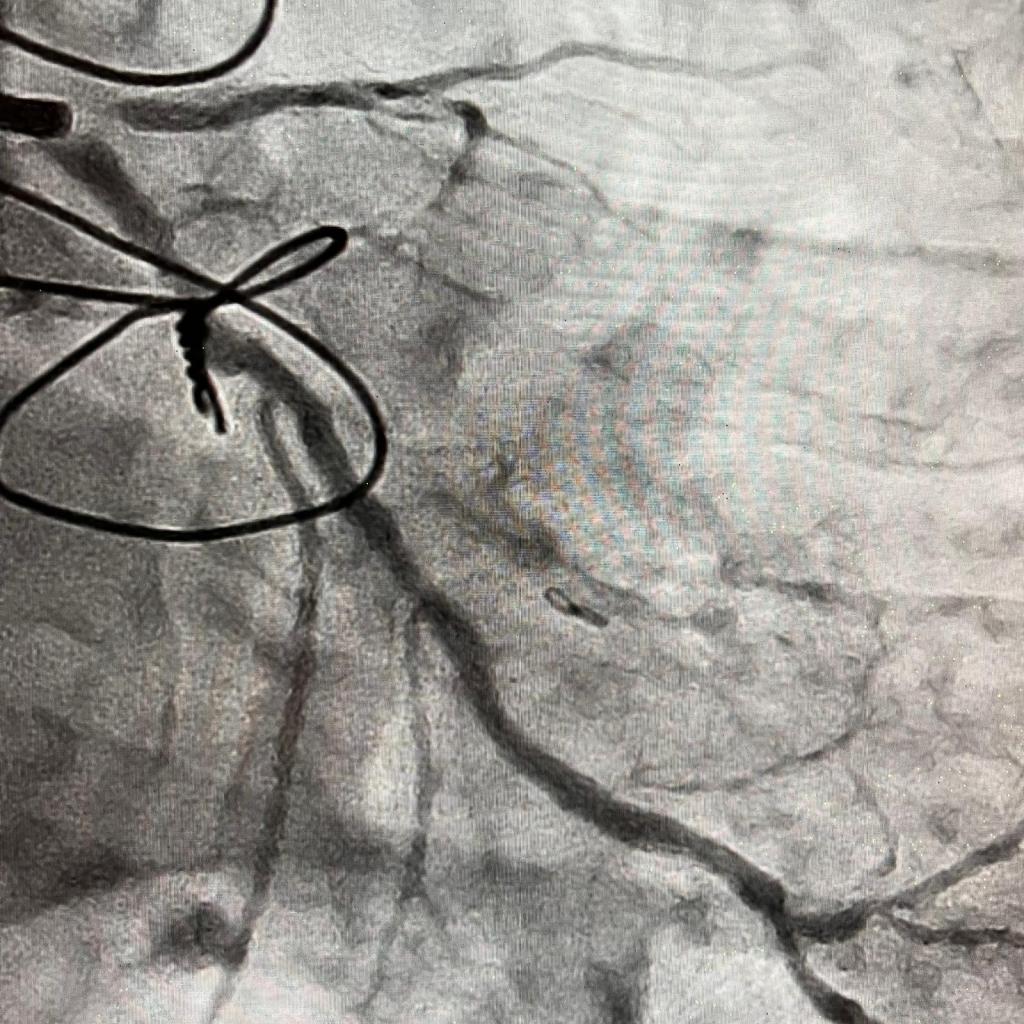

We ended up wiring the LM into the LCX followed by atherectomy with a 1.5 burr. We were unable to wire the proximal LAD from the LM because the ostium was obstructed by the calcium nodule.

And here is the final result.

You can see that the LCX is technically a first OM that supplies a major portion of the lateral wall with its 5(!) branches.